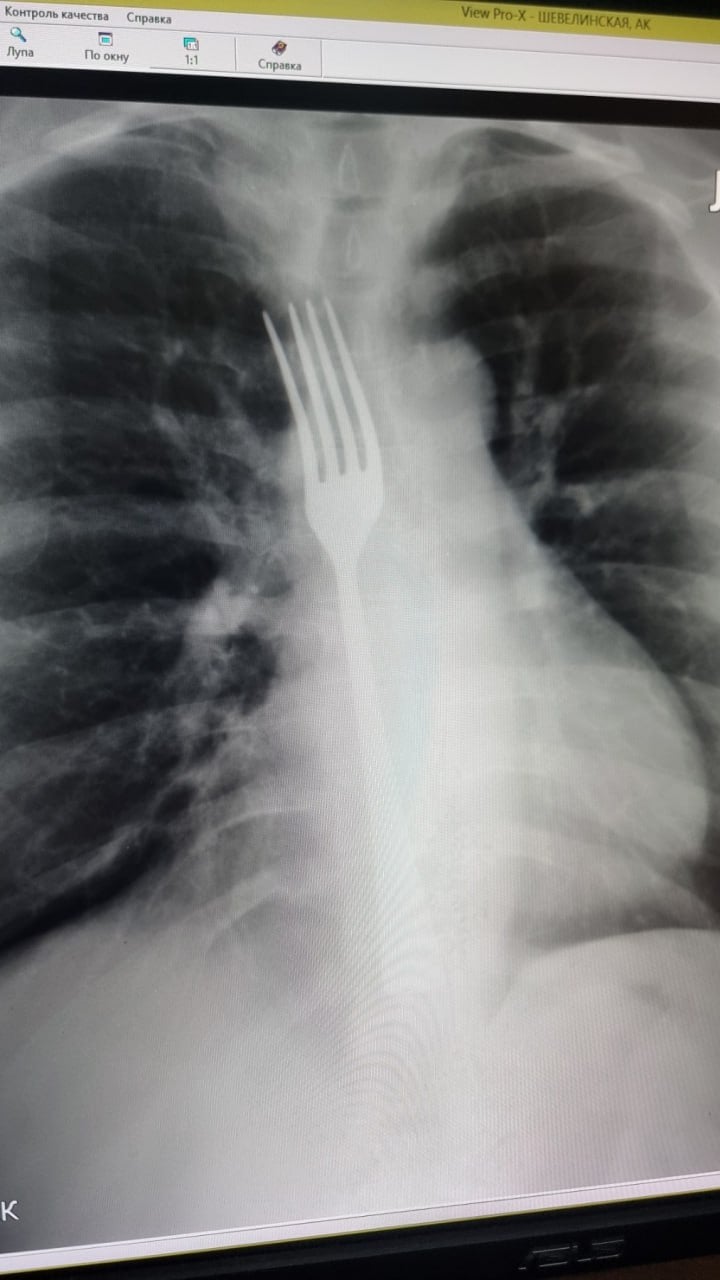

Девушка попыталась вызвать рвоту своими силами. Для этого она использовала черенок от вилки. Но «лечение» пошло не по плану: вилка проскользнула в пищевод и застряла в нем.

Пришлось срочно вызвать скорую помощь. Девушку сразу же после обследования отправили в операционную. Благодаря слаженной работе врачей удалось избежать серьезных осложнений. К счастью, вилка не вклинилась в пищевод, что существенно бы осложнило помощь. Под наркозом инородный предмет сместили в желудок, а уже оттуда извлекли во время открытой полостной операции.